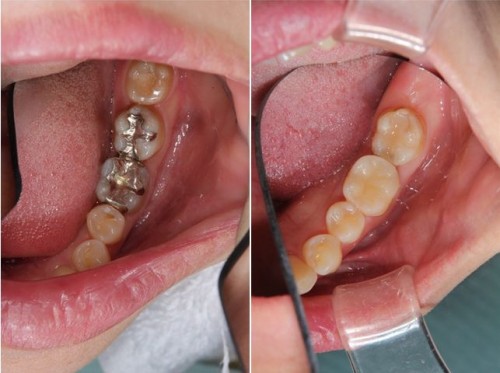

オールセラミックインレーの術前術後です。左の写真は削った後です。歯の周りに黒い線が見えますが、圧排糸という歯と歯ぐきの境目を明瞭にする為の物です。右が術後ですが、歯の色と同化しており、ほとんど区別がつきません。また、汚れをはじく性質を持っているため、歯ぐきに炎症が起きにくいです。変色が起きないため半永久的に、この状態を保ってくれます。

銀歯を外してセラミックインレーを装着した状態です。

セラミックインレー

費用11万円

リスクとして歯を削る量が多いため痛みが出る可能性と強い力によって割れる可能性がある。